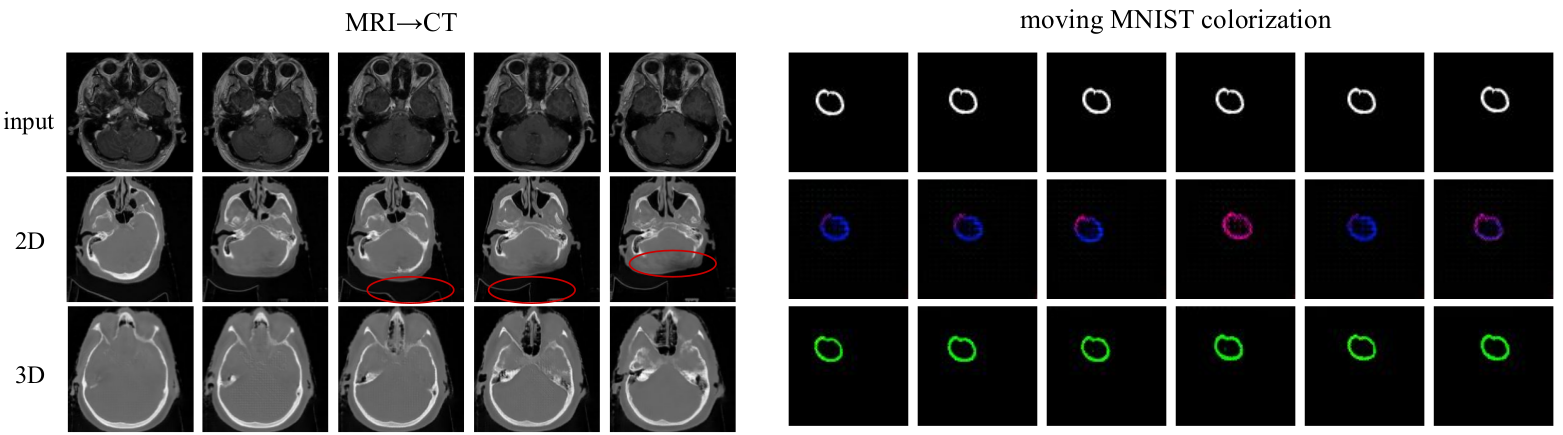

The experiment on colorization of MNIST videos showed that the “random” model is able to colorize individual frames but cannot preserve the color throughout the whole sequence. The choice of batch selection, however, is important: the sequential and const-loss models learned to preserve the same color throughout the sequence even though they did not have access to previous frames. However, we should mention that all models that succeeded in this task collapsed to colorizing digits with a single (blue-green) color even though the training data had 20 different colors.

The experiments on MRI-to-CT translation showed that all per-frame translation methods produce image volumes that do not capture the real anatomy (e.g. shape of the skull, nasal path and eyes vary significantly within the neighboring frames), whereas the proposed 3D method gives a continuous and generally more realistic results for both CT-MRI and GTA segmentation-to-video tasks (Table 4). The CT-to-MRI task is harder since it requires “hallucinating” a lot of fine details and on this task 3D model outperformed random with a significant margin (bold numbers). On a simpler MRI-to-CT task random and 3D models performed similarly within the limits of statistical error.